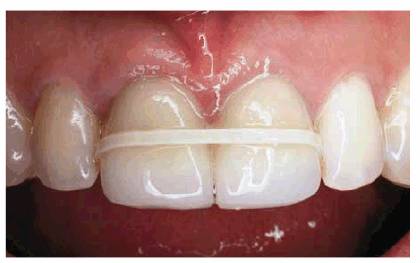

esthetics (Figures 23-13A, 23-13B and C).

Figure 23-13A: When a diastema of this size is to be closed using composite resin bonding, a hybrid material should be chosen on the lingual surface for strength.

Figure 23-13B and C: To obtain a maximum "glaze" or polish to match existing enamel, a microfilled composite resin can be used on the labial surface. Note the glazed appearance of the labial microfilled polished composite resin.